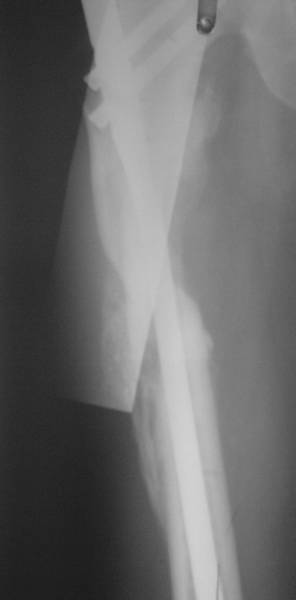

Нашел в архиве наш проблемный остесинтез  на таком-же штифте с  варусным

смещением проксимального отломка, который ,правда, успешно

консолидировался в срок.